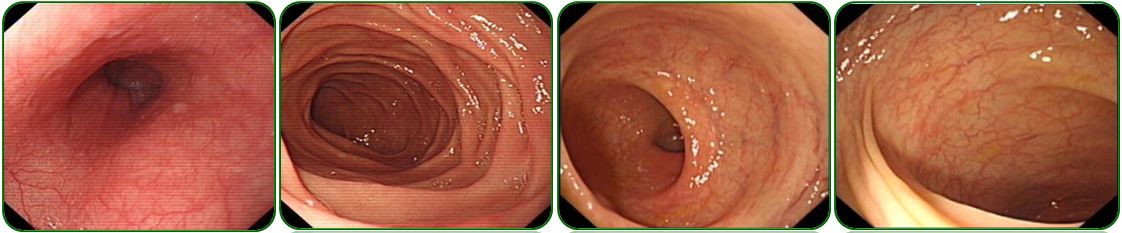

胃镜、肠镜未见异常,如图6;

图6 胃镜、肠镜检查